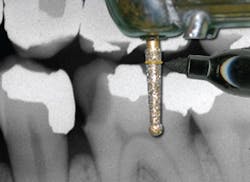

Use the Endo Access bur at a predetermined length (marked with a Sharpie® permanent marker) so as not to perforate the furcation (Fig. 3).